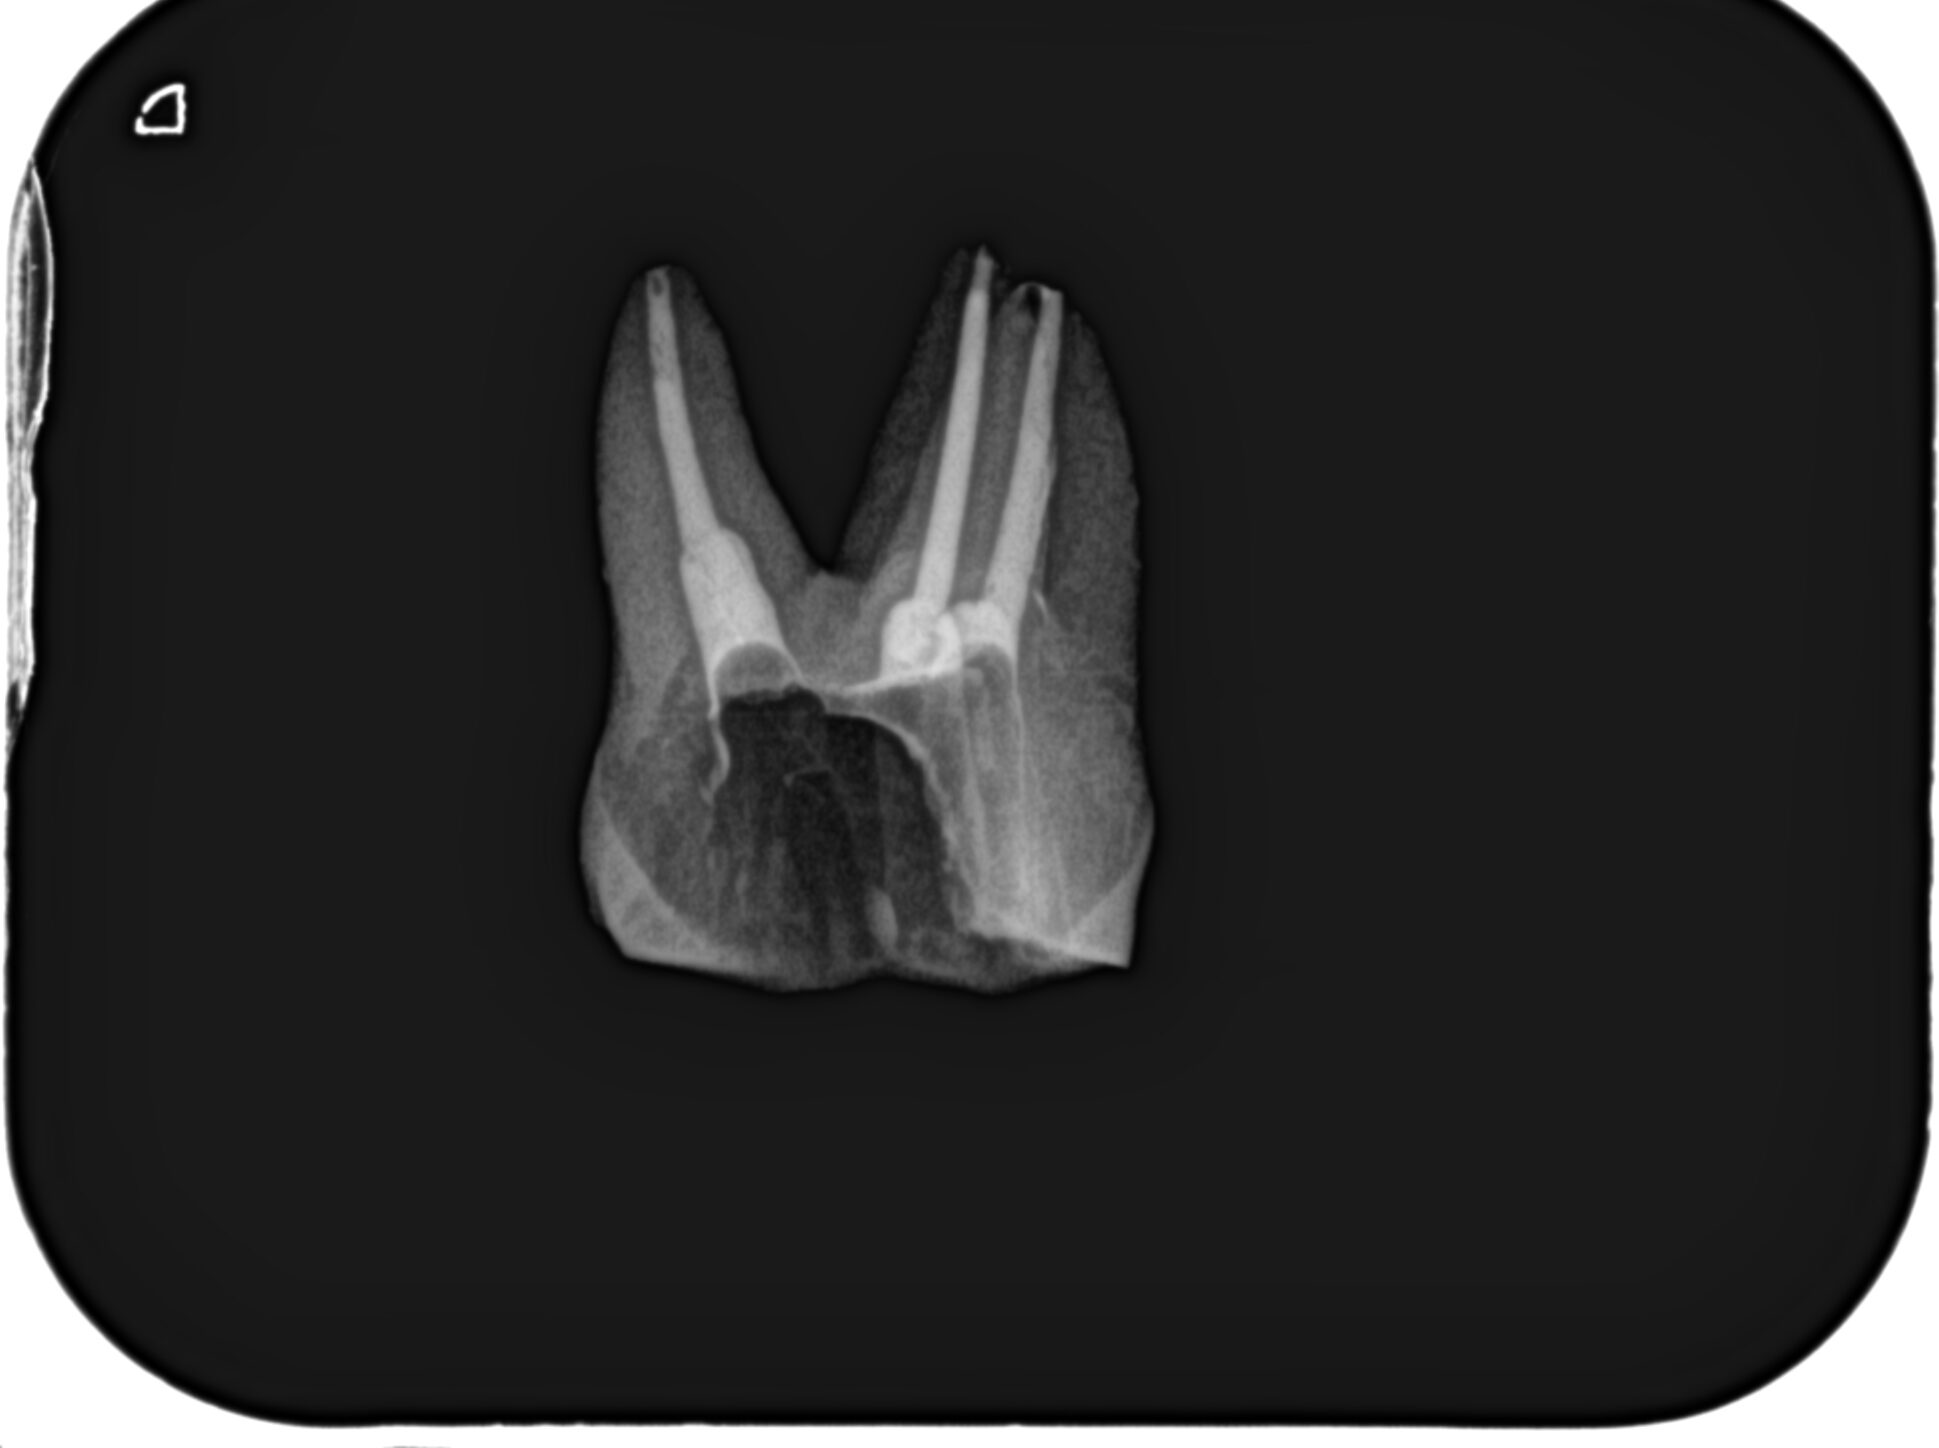

再根管充填し、PAを撮影した。

問題はないだろう。

次が以下である。

P根は根管がうっすら見えているが穿通しなかった。

MB,DBはC+ Fileを使用しても穿通せず、HyFlex EDM #10.05, RaCe EVO #10.04,#10.02を使用しても穿通しなかった。

つまり、閉鎖根管である。

術後のPAは以下だ。